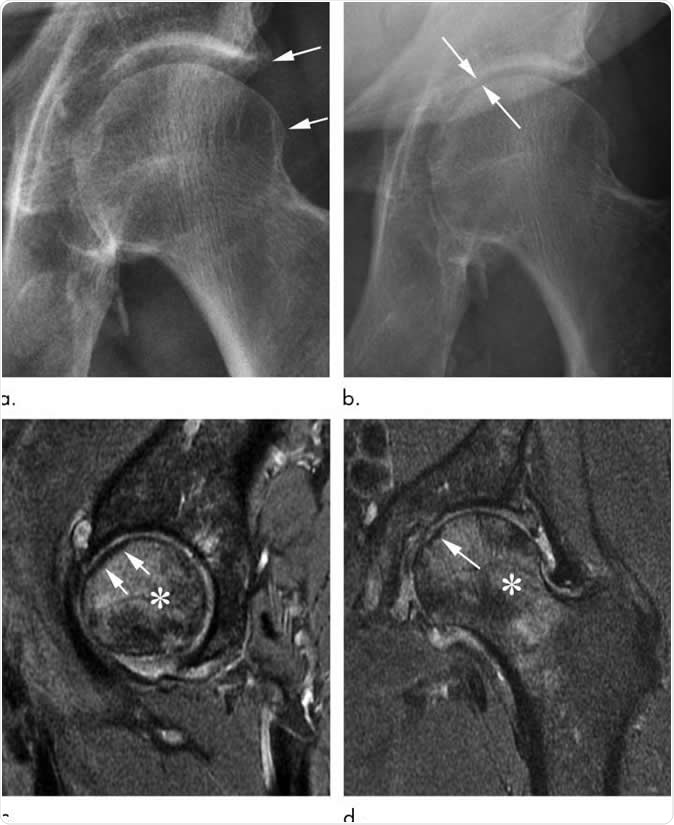

Rapid progressive osteoarthritis joint space loss (type 1) and subchondral insufficiency fracture in a 53-year-old man who presented with hip pain. (a) Anteroposterior left hip radiograph shows mild osteophytic changes (arrows) and no joint space loss. This patient was referred for intra-articular corticosteroid injection. (b) Seven weeks after injection, he returned with worsening hip pain. Repeat anteroposterior left hip radiograph shows accelerated loss of joint space (arrows). (c) Sagittal intermediate-weighted fat-suppressed MRI obtained at the same time as b shows a linear subchondral hypointensity representing subchondral insufficiency fracture of the anterior superior femoral head with subtle flattening of the overlying articular surface (arrows). Extensive bone marrow edema extends to the femoral neck. (d) Corresponding coronal intermediate-weighted fat-suppressed MRI enables us to confirm the presence of a subchondral insufficiency fracture (arrow) and depicts the true extent of bone marrow edema. Image Credit: Radiological Society of North America